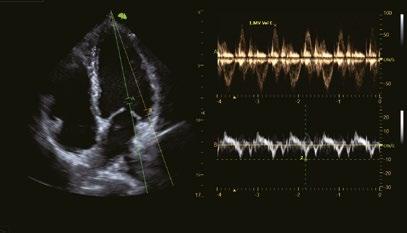

Multi-Doppler

Kombination von PW/PW, PW/TDI, TDI/TDI zur gleichzeitigen Bewertung von Wandbewegung, Asynchronie und Hämodynamik.

Apikale 4-Kammer-Ansicht zeigt segmentale und globale longitudinale Dehnung des linken Ventrikels

Mit einem Klick die Auswurfrate (EF) automatisch berechnen.

Vierkammer Ansicht

Mitral-Klappe PW